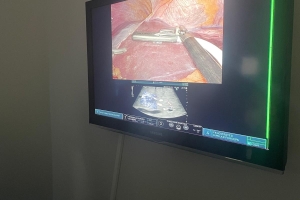

Uluslararası Cerrahi Gastroenteroloji ve Onkoloji Derneği (UCGOD) olarak, International Association of Surgeons, Gastroenterologists and Oncologists (IASGO) iş birliğiyle 17–18 Kasım 2025 tarihlerinde Cerrahpaşa Tıp Fakültesi Prof. Dr. Murat Dilmener Hastanesi’nde gerçekleştirdiğimiz Intraoperative Ultrasonography (IOUS) Kursunu başarıyla tamamladık.

İki gün süren program boyunca, yurtiçi ve yurtdışından katılan cerrahlar; açık ve robotik cerrahide intraoperatif ultrasonografinin temel prensiplerini, vasküler ve biliyer anatomide ileri görüntüleme tekniklerini ve ameliyathane koşullarında uygulama pratiğini deneyimleme fırsatı buldular.